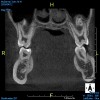

Fig 7. Panoramic radiograph, 14-year-old brother.

Figure 7

Figure 5 through Figure 12 exemplify what currently may present in private dental practices with these types of patients. Four brothers aged 14 years to 27 years all suffered from obstructed airways; high incidence of caries of dentin, enamel, and cementum; moderate periodontal disease; collapsed vertical; undiagnosed OSA; and the potential for increase in comorbidities such as diabetes, cardiovascular disease, dementia, cancer, high blood pressure, and others. Symptomology was presented throughout the young lives of the brothers in this family. The parents were unaware that the dental agenesis and premature permanent tooth extraction could have led their sons into severe health issues as they matured.

Swift intervention took place with caries control, periodontal care, orthodontic evaluation for arch form development to aid in the development of facial bones and creating an improved upper airway with nasal patency. These interventions were followed up with definitive implant therapies and rapidly advancing restorative technology and materials. Thus, not only were these young men's smiles restored, they also were provided with the opportunity to regain their dignity when they become confident with their new smiles.